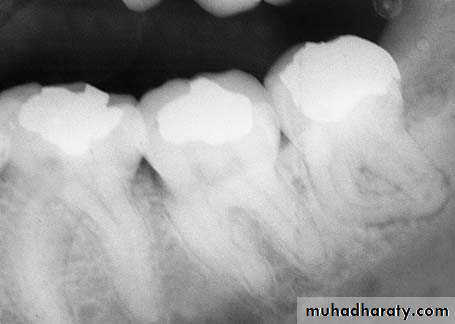

If the root or tooth is in an intimate contact to the inferior alveolar nerve, damage can be prevented or minimized only by preoperative radiographic diagnosis and surgical removal of the tooth or root.

This clinical entity is a localized osteitis involving either the whole or a part of the condensed bone lining a tooth socket , the lamina dura . the condition is characterized by an acutely painful tooth socket containing denuded bone and broken down blood clot.Dry socket , also termed alveolar osteitis ,fibrinolytic alveolitis and alveolitis sicca dolorosa exodontias .

It is characterized by increasingly severe pain which usually starts on the 2nd or 3rd post extraction day in and around the extraction site .lasting for between 10 -14 days .

the normal post extraction blood clot is lost from the socket and its walls is denuded .